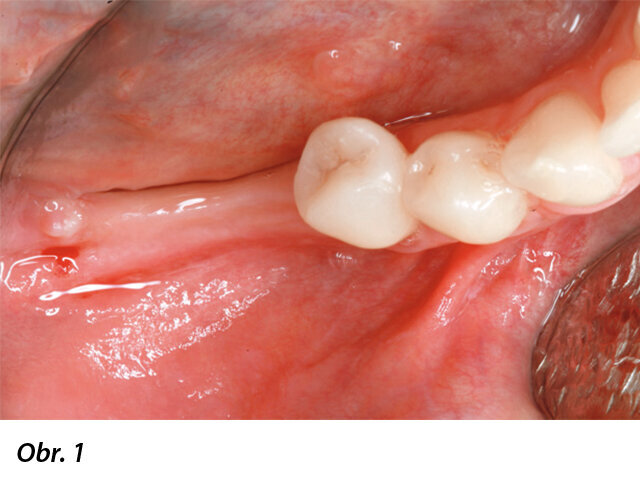

Okluzální pohled na tenký hřeben v distální části dolní čelisti. V oblasti keratinizované gingivy na středu hřebenu byl proveden mukoperiostální řez. Pro zajištění chirurgického přístupu byly provedeny dva rozbíhavé vertikální řezy, jeden meziobukálně od prvního premoláru a jeden šikmý vertikální řez na nejdistálnější straně krestálního řezu.

Recipientní oblast kosti byla opatřena několika dekortikačními otvory a autogenní kost byla odebrána ze zevního šikmého hřebene za použití poloviny z 4mm trepanu.

Bukální pohled po umístění směsi autogenní granulované kosti a granulí Geistlich Bio-Oss v poměru 1 : 1. Všimněte si, že membrána Geistlich Bio-Gide je před umístěním štěpu fixována na hřebeni.

Bukální pohled na jednu membránu Geistlich Bio-Gide fixovanou titanovými piny. Piny mají průměr 1 mm a jsou v kortikální kosti dolní čelisti stabilní. Všimněte si, že fixovaná membrána zcela imobilizuje kostní štěp díky tomu, že jej „obaluje“ jako „klobásu“.